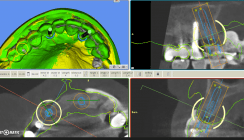

Anschließend wurde ein Intraoralscan (TRIOS®, 3Shape) der betroffenen Region mithilfe der Best- Fit-Option in die DVT-Aufnahme gematcht, um die raumgeometrische Zuordnung der Implantatund Hülseneinstellungen mit den Modelldaten für die Schablonenkonstruktion zu erlangen. Die virtuelle Konstruktion der Navigationsschablone erfolgte mithilfe der Freeform-Software Plasty-CAD (3DIEMME; Abb. 4), welche anschließend im Stereolithografie-Druckverfahren (DWS) hergestellt wurde.

Nach erfolgter okklusaler Exposition wurde die Einprobe und Überprüfung der Passung der Navigationsschablone vorgenommen. Danach wurde die Pilotbohrung mit einer modifizierten Lindemann- Fräse unter Kühlung mit Kochsalzlösung bis zum Erreichen des Tiefenstopps im Furkationsbereich durchgeführt. Dies wurde anschließend endoskopisch kontrolliert (Abb. 5).

Die Erweiterungsbohrung erfolgte mit einem modifizierten Rosenbohrer unter Kühlung bis zur Tiefenmarkierung (Abb. 6). Auch diese Bohrung wurde anschließend mit dem Endoskop visuell kontrolliert.